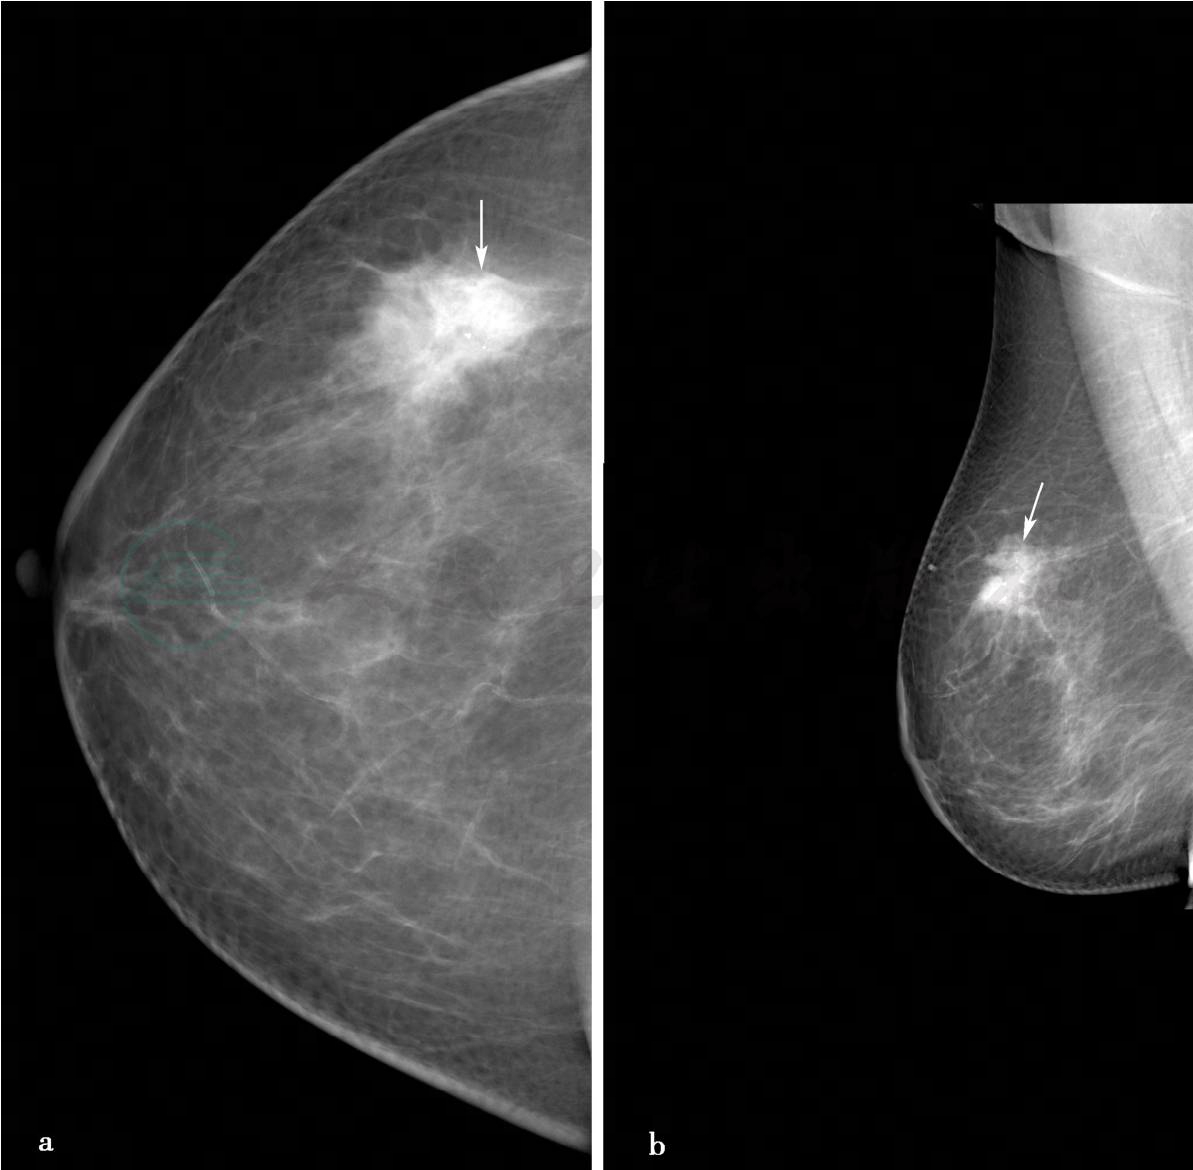

(3)病例3:

X线及超声检查。

图3 图3a,右乳X线头尾位。图3b,右乳X线内外斜位。图3c,右乳病变局部放大片。X线显示右乳呈脂肪型乳腺,右乳外上不规则分叶状肿物(图箭头所示),大小约1.8cm× 2.3cm,边缘呈蟹足状浸润,其内可见2枚点状钙化,皮下脂肪层清晰,皮肤及乳头正常。图3d,右乳病变二维超声图,超声显示右乳外上1.5cm×2.0cm低回声反射区,形状不规则,边界不清楚,边缘呈蟹足状浸润,内部回声不均匀,肿物后方可见声影。图3e,右腋下淋巴结二维超声图,右腋下可见1.3cm× 2.3cm肿大淋巴结,正常淋巴结门结构消失